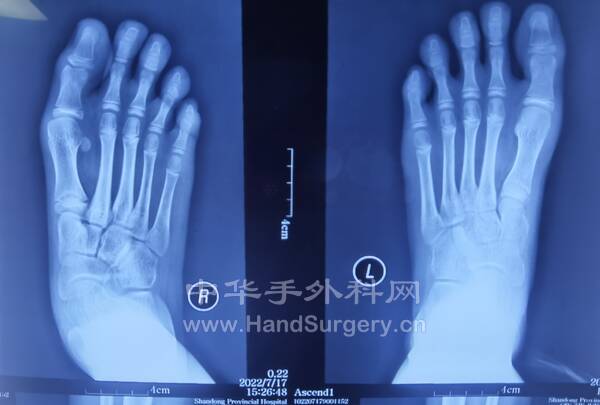

13岁女孩,双足拇外翻,老师建议手术治疗。